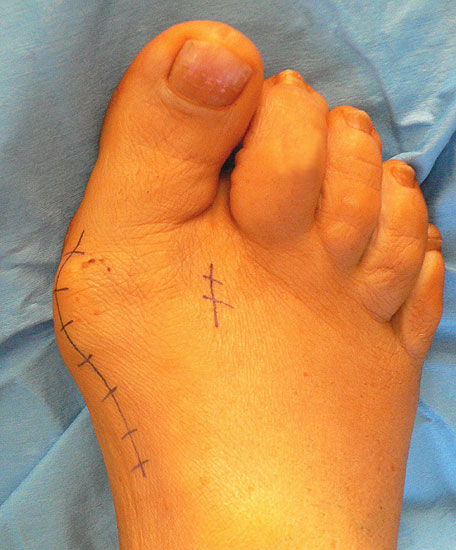

Abbildung 13

Bei sehr schräg verlaufendem Tarsometatarsalgelenk ist darauf zu achten, mit den proximalen Schrauben nicht das Gelenk zu verletzen.